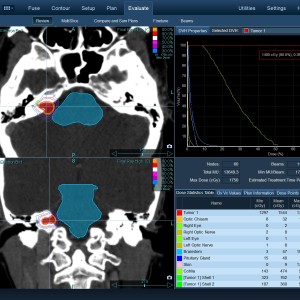

Στις παρακάτω φωτογραφίες θα δείτε παραδείγματα πλάνων θεραπείας καρκινικών όγκων με CyberKnife. Παρατηρήστε πόσο κοντά στους υγιείς ιστούς βρίσκονται οι καρκινικοί όγκοι που χρειάζεται να ακτινοβοληθούν. Μόνο με το CyberKnife και το προσωπικό πλάνο θεραπείας, μπορούν να ακτινοβοληθούν οι όγκοι χωρίς να πληγούν οι παρακείμενοι υγιείς ιστοί.

Μόνο με το CyberKnife και την κατάλληλη σχεδίαση της θεραπείας από έμπειρο νευροχειρουργό, μπορεί να ακτινοβοληθούν οι όγκοι χωρίς να επηρεαστούν από την ακτινοβολία οι υγιείς ιστοί. Αυτό εξασφαλίζει τη μέγιστη δυνατή απόδοση της ακτινοχειρουργικής θεραπείας των όγκων.

Με κόκκινο χρώμα περιγράφεται η περιοχή του όγκου.

Με μπλε, κίτρινο και πράσινο χρώμα περιγράφονται οι υγιείς ιστοί που δεν πρέπει να ακτινοβοληθούν.

Παρατηρήστε πόσο κοντά βρίσκεται ο όγκος με τους υγιείς ιστούς.